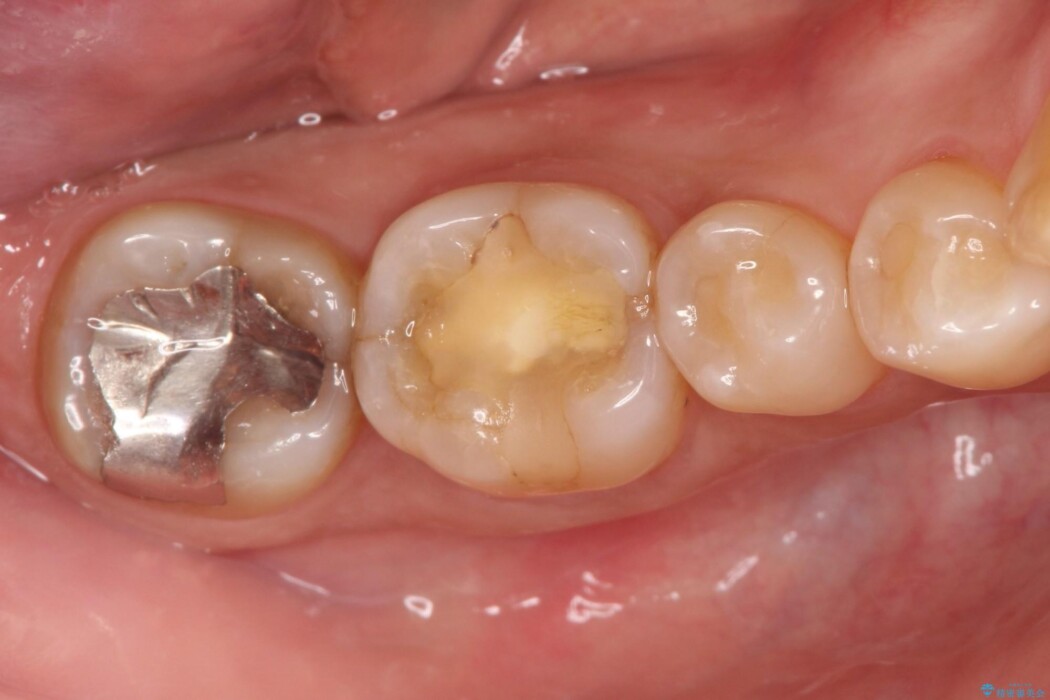

歯髄炎の治療は、歯髄を除去する根管治療と、歯の形や機能を回復させる被せ物(クラウン)の治療が必要です。

根管治療後の最終補綴物(クラウン)の精度は予後に大きく影響します。